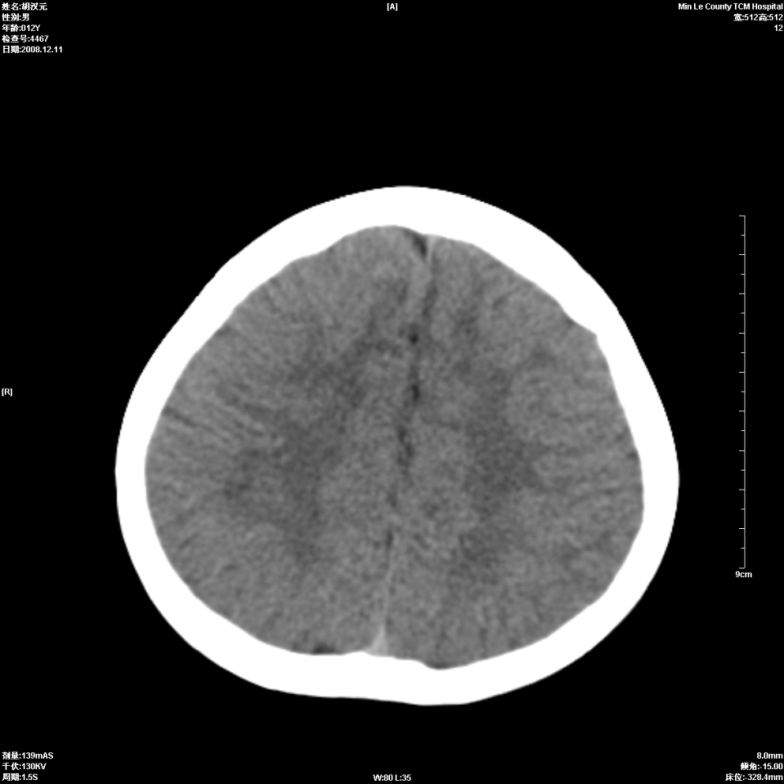

标题: PED1681:头疼发热约一周 [打印本页]

标题: PED1681:头疼发热约一周

颅脑未见确切异常。必要时进一步检查,如mri、脑脊液检查。

两侧顶部近灰质处白质密度降低,是否炎性改变

颅脑ct轴位平扫颅内未见明确异常;建议必要时复查或行进一步检查。

两侧顶部近灰质处白质密度降低,建议mri